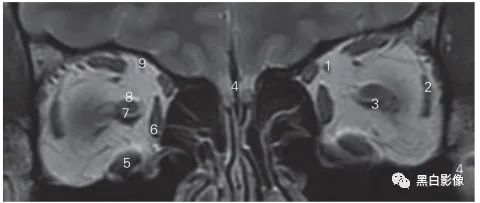

图5-1 经嗅球的冠状断层MR T1加权图像

1 嗅束沟 olfactory sulcus 2 嗅球 olfactory bulb

3 内直肌 medial rectus 4 鼻中隔 nasal septum

5 下直肌 inferior rectus 6 下鼻道 inferior nasal meatus

7 下鼻甲 inferior nasal concha 8 上颌窦 maxilary sinus

9 筛窦 ethmoid sinus 10 视神经 optic nerve

11 嗅池 olfactory cistern 12 眶回 orbital gyrus

13 直回 gyrus rectus 14 额叶 frontal lobe

15 大脑镰 cerebral falx